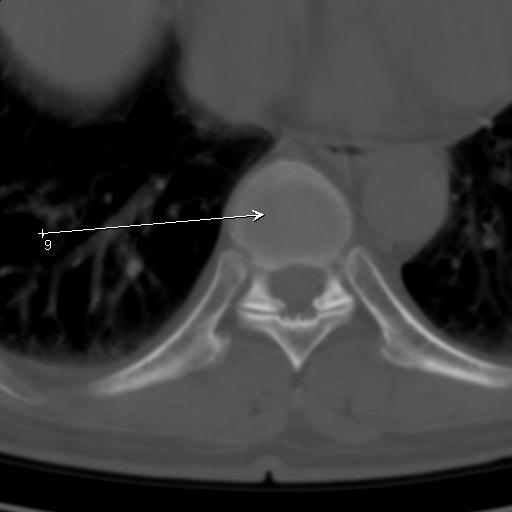

标题: CT25189:胸椎ct,请会诊!

既往食管癌,现行ct检查!

仅见椎体退行性改变

中上段食道癌,椎体轻度退变。

椎体退行性改变,食管癌。

支持中上段食道癌,椎体轻度退变,必要时做ect。

支持中上段食道癌,椎体轻度退变。